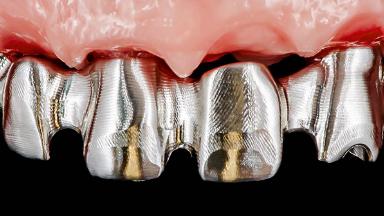

Rehabilitating an Edentulous Maxilla with a Fixed Dental Prosthesis Following Provisional Immediate Loading

This case features the flapless computer-guided placement of 7 bone-level implants, distributed to provide maximal support for the prosthetic framework. A rigid one-piece metallic framework was utilized as an interim restoration to reduce the risk of fracture associated with this prosthetic design. As part of the clinical examination, the SAC Assessment Tool was used, resulting in a surgical and restorative risk classification as “complex”.

Prosthesis Type FDP

SAC Level Complex

Defining Characteristics Fully edentulous upper jaw to be rehabilitated with an implant-borne fixed dental prosthesis

Loading Protocol Immediate